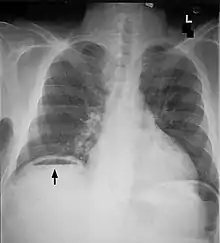

| Frontal chest X-ray. The air bubble below the right hemidiaphragm (on the left of the image) is a pneumoperitoneum. | |

Another pneumoperitoneum on chest X-ray.